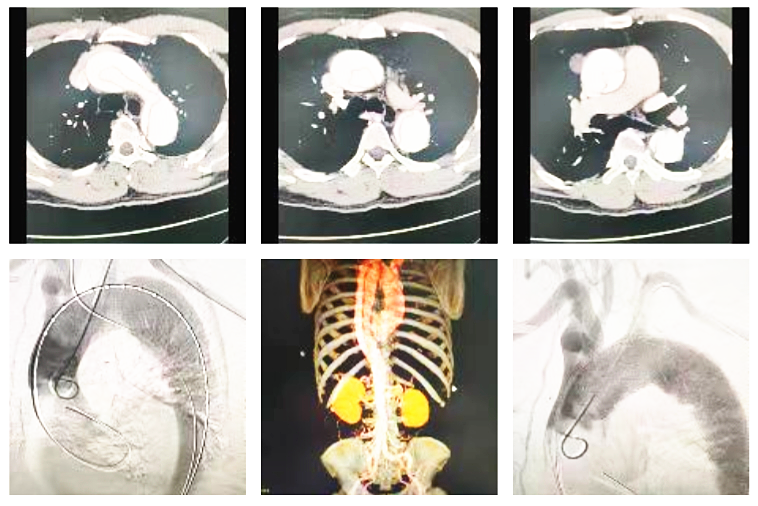

胸心血管外科以“敬业福”换患者“健康福”。除夕前有两名患者在家时出现胸闷气促、呼吸困难、右下肢酸胀的症状,立即到我院就诊,胸心血管外科团队立即进行检查,定制手术方案,高质量完成2台肺栓塞取栓手术,收获患者满满好评。

“新冠”后,潜在肺栓塞不容忽视!疫情政策调整后,肺栓塞高发,多名患者无下肢深静脉血栓,无其他高危因素,新型冠状病毒感染却成为一个独立的危险因素。胸心血管外科开展了多台肺栓塞溶栓术,均取得满意效果。

【先进技术】胸心血管外科成功为两名先心病患者行房间隔缺损介入封堵术,两名患者的手术均在一个小时内便圆满成功。介入封堵术取代外科手术,小切口解决大问题。手术时间短、创伤小、恢复快,患者术后6-8小时即可下床活动,简单解决患者难题,有效提高了患者生活质量。术后,两名患者都表示:“感谢主任为我们制定的手术方案,没想到一个小小的伤口就解决了我们的问题!”